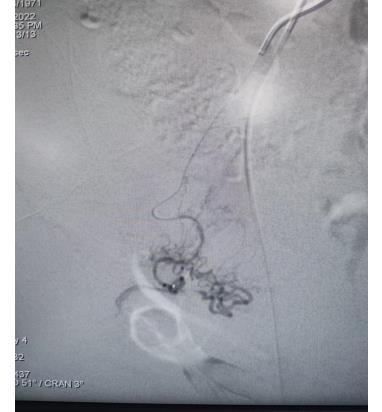

子宮動(dòng)脈栓塞術(shù)屬于血管介入性治療,方法是于股動(dòng)脈穿刺進(jìn)針插入導(dǎo)管,在X射線造影下定位進(jìn)入兩側(cè)子宮動(dòng)脈,注入栓塞劑完全栓塞子宮動(dòng)脈,從而達(dá)到止血或讓子宮肌瘤和病灶缺血壞死的目的;2022年12月6日,在崔旭輝主任、孟慶槐副主任醫(yī)師、馬力主治醫(yī)師等我院介入團(tuán)隊(duì)協(xié)作下,成功為患者進(jìn)行了雙側(cè)子宮動(dòng)脈栓塞術(shù),術(shù)后患者子宮異常出血停止,效果立竿見影,患者病情恢復(fù)良好。

左側(cè)子宮動(dòng)脈栓塞前后對(duì)照

右側(cè)子宮動(dòng)脈栓塞前后對(duì)照